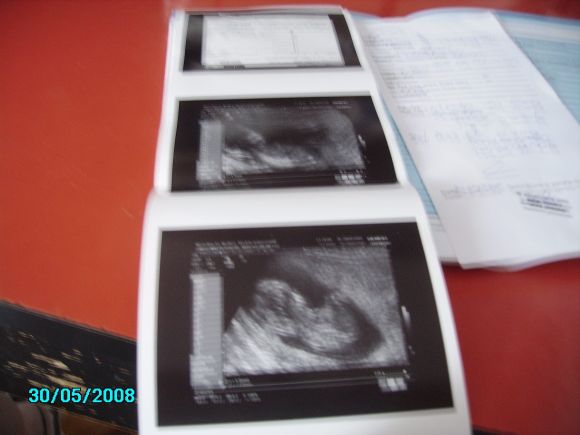

Márti: Kitartás! 2 hét az nem olyan sok! Viszont a méhszájon tapadó lepényről én is azt hallottam, hogy ahogy nő a méh, feljebb kúszhat. Drukkolok. És nagyon gratulálok a babucid méreteihez és az első sztárfotókhoz!